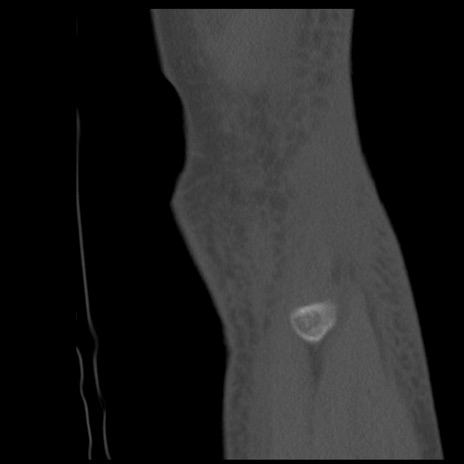

症例28 右膝関節CT(矢状断像)

右膝関節CT